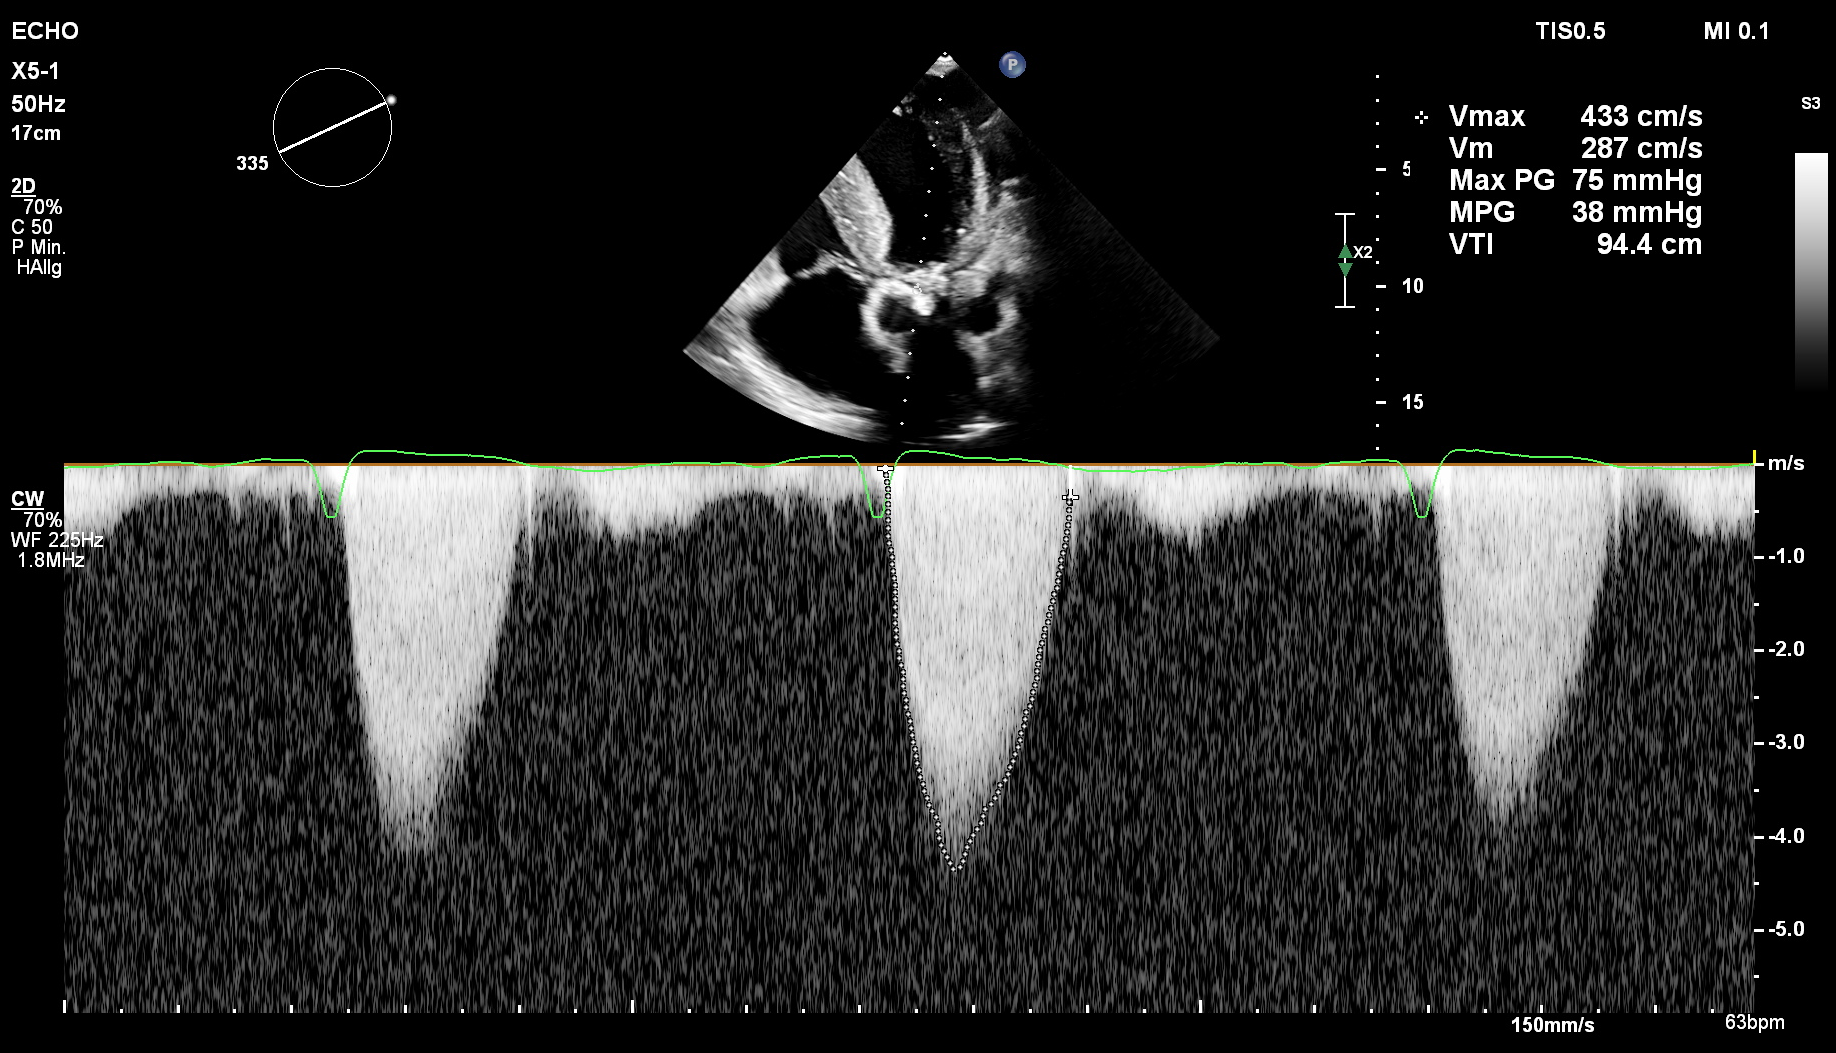

cw-Doppler: AoV-Stenose

Darstellung der AoV-Stenose im cw-Doppler.

Erstdiagnose einer schweren Aortenklappenstenose mit verminderter Separation der ausgeprägt sklerosierten Klappen bei einem Hämodialyse-Patienten mit in den letzten Tagen progredienter Dyspnoe. Die weitere Evaluation erfolgt mittels Dopplersonografie.